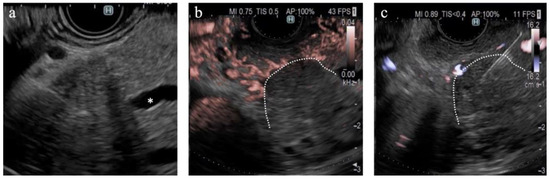

Figure 6.

A case of pancreatic neuroendocrine neoplasm. (a) B-mode shows a hypoechoic tumor with a well-defined margin. (b) eFLOW shows linear vessels in the lesion. (c) On DFI, the tumor is occupied by dilated vessels. (d) Endoscopic ultrasound-guided tissue acquisition.

The findings of this study demonstrate the utility of DFI for purposes other than the differential diagnosis of SPLs. DFI enabled the identification of small hypervascular lesions within 10 mm, which was unexpected (Figure 4c,d). The frame rate of DFI is higher than those of B-mode and eFLOW; thus, DFI can be used as a screening evaluation for patients with Multiple Endocrine Neoplasia type 1 or von Hippel–Lindau disease [41,42]. Hypersensitivity to vascular structures aided the avoidance of thick vessels during the EUS-FNB procedure (Figure 5). DFI, rather than eFLOW, can be used to define the vessels more precisely in patients with NEN. This technique enables the effective acquisition of tissue samples without major bleeding. The absence of linear vessels in pancreatic cancer lesions can aid the detection of tumor margins (Figure 6). A pancreatic cancer lesion without a detectable margin was observed on B-mode and eFLOW in this case, and the initial EUS-FNB result was a false negative. Subsequently, DFI was performed, and the normal vessels in the surrounding pancreatic parenchyma near the tumor margin disappeared. The diagnosis was confirmed by puncturing the areas without vessels on DFI. Thus, DFI can be considered a novel tool for determining the differential diagnosis of pancreatic cancer in the future.